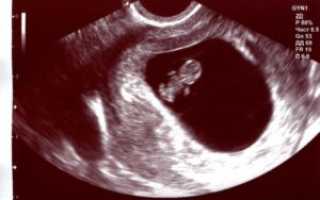

УЗИ на 9 неделе беременности

На УЗИ плода на 9 неделе определяется толщина плаценты и общее состояние пуповины. При помощи допплера, будущая мама может отметить частоту сердечных сокращений малыша. Хотя многие внутренние органы уже достаточно развиты, это не всегда можно увидеть на УЗИ на 9 неделе.

Внутренние органы крохи еще могут выступать в виде пупочной грыжи, но нет повода для беспокойства, ведь это совершенно нормальное явление.

На девятой акушерской неделе беременности ультразвуковое обследование позволяет услышать биение сердечка ребеночка. Помните, что акушерский срок немного отличается от эмбрионального возраста плода. Это примерно 1-2 недели.

В норме сердце плода бьется 140-160 ударов в секунду. При обследовании частота может повышаться. Ведь это стресс, и малыш волнуется. Также в такой ситуации может сокращаться матка.

В данный срок специалист УЗИ оценивает состояние жёлтого тела, которое вырабатывает гормон прогестерон. Сейчас недостаток этого вещества крайне опасен и может привести к прерыванию беременности.